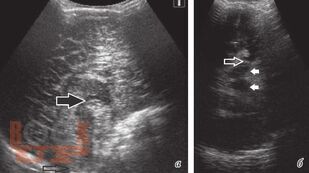

Учебное пособие посвящено вопросам организации и проведения нейровизуализационной диагностики у детей при энцефалитах и менингитах на различных этапах заболевания. В книге указаны особенности визуализации энцефалитов в зависимости от этиологии и тяжести течения заболевания.

Мы приводим разбор возможностей диагностических методик и усовершенствованный алгоритм нейровизуализационной диагностики при нейроинфекциях у детей.